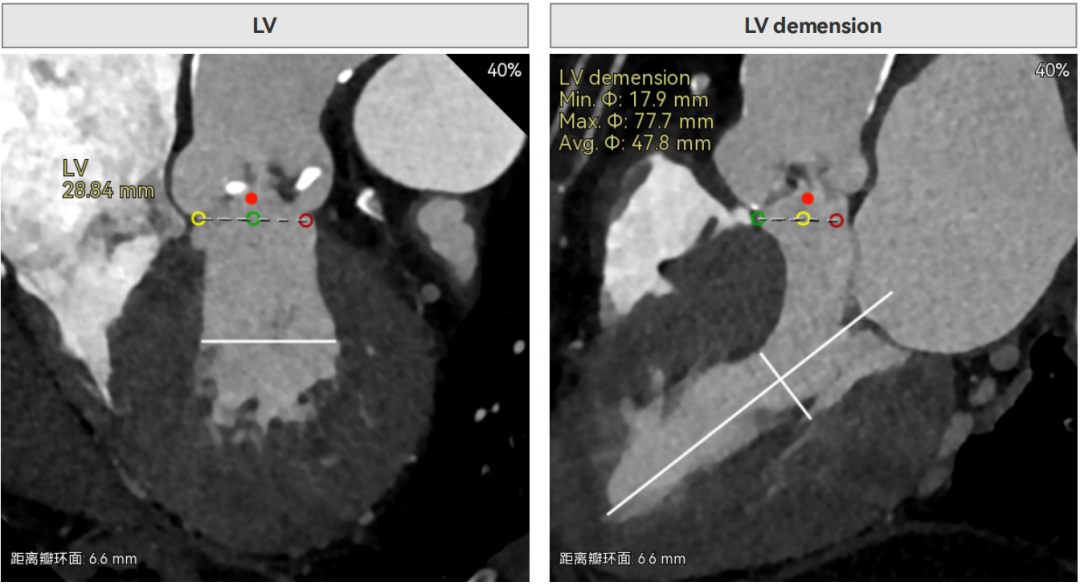

主动脉瓣环周长径21.9mm,小瓣环,LVOT直筒型结构;三叶瓣,左右融合(功能型二叶瓣),瓣叶轻微增厚并重度钙化,钙化主要分布在无冠窦瓣叶边缘及左右交界融合处,瓣上限制较重。

窦部空间适中,STJ内径偏小,升主动脉内径可。

左室内径较小,但合并轻度反流,低循环崩溃风险,室间隔膜部长度<3mm,有一定术后起搏器植入风险。